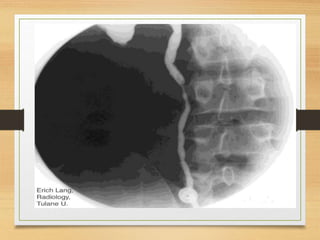

CASE 2

• A 35-year-old man presents to the emergency

department with intermittent right loin to groin pain

and visible hematuria. He had history of passing

stones . What is the likely cause?